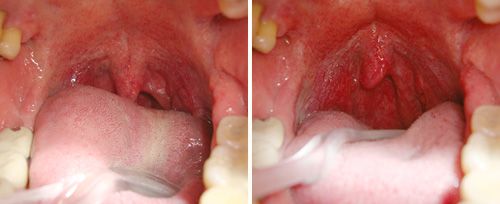

Grâce à l’action du laser Er:YAG en mode SMOOTH®, le traitement stimule le collagène et entraîne une rétraction des tissus du voile du palais et de l’oropharynx, responsables de l’obstruction partielle des voies respiratoires.

– Résultat : un passage de l’air facilité, une réduction significative du ronflement et une meilleure respiration nocturne.